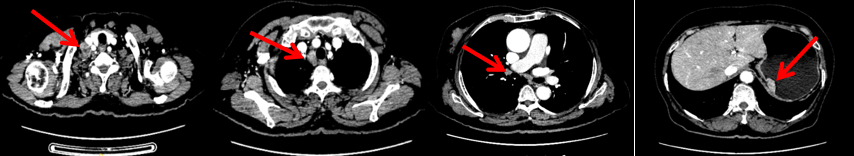

颈胸腹盆腔CT

右乳外上象限占位,考虑乳腺癌;右侧锁骨上、上纵隔及右肺门多发淋巴结转移(较大者24*15mm)。胃贲门处小弯侧胃壁明显增厚(26*12mm),考虑胃癌可能,周围脂肪间隙清;颈部未见明确异常。头颅MR未见脑转移。

1.右乳外上象限乳腺癌病灶(22*16mm),对比2023-04-14 CT(26*24mm)较前缩小,FDG代谢活跃。右侧腋窝小淋巴结(5mm),较前稍缩小,代谢不活跃。右侧锁骨上区、上纵隔淋巴结转移瘤(24*18mm),现大小同前相仿,代谢活跃(SUV:6.7)。

2.现胃贲门部术后改变,术区未见明显异常活性灶。

3.左乳、左侧胶窝术后改变,未见明显异常活性灶。双肺小结节。考虑炎性结节可能,建议复查;双肺门及纵隔另反应性淋巴结。

2024-11-5复查CT:右乳外上象限占位(11mm×9mm),较前明显缩小;上纵隔及右肺门多发淋巴结转移缩小;右锁骨上区淋巴结较前增大。余部位未见肿瘤转移及复发征象。